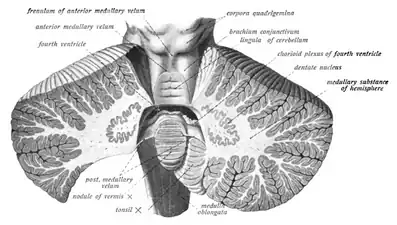

Midsagittal section of the brainstem. Coronal section of the cerebellum.

Coronal section of the cerebellum. Arbor vitae and cerebellar peduncles.

Arbor vitae and cerebellar peduncles.